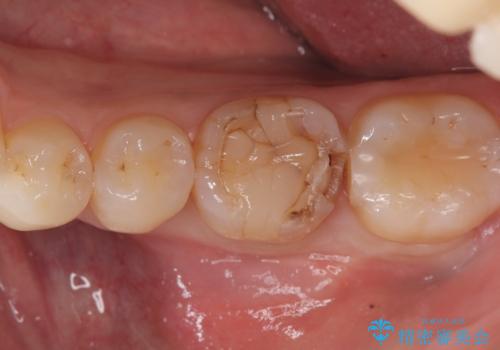

- 主訴:強く噛んだら歯がポロポロ欠けてきた。

左下6番目の歯の咬合面にプラスチックの材料が詰まっており、歯質がドーナツ状にしか残っていなかったため、歯質幅が比較的薄かった場所が欠けてしまったようでした。

今後の破折リスクを説明し、セラミッククラウンでのやり替えとなりました。

頬舌的レジンインレーが入っており、歯質幅の薄かった且つ強く咬合していた遠心側歯質が欠けてしまっていました。また新しい窩洞のインレーを入れても、近心側歯質の破折のリスクは抱えたままになることから、クラウンでの修復をおすすめし審美性・適合性のよいセラミッククラウンでのやり替えとなりました。